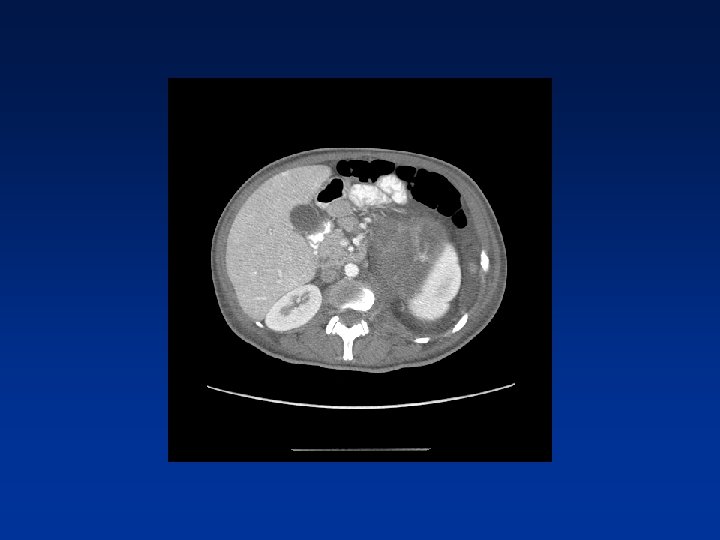

CASE